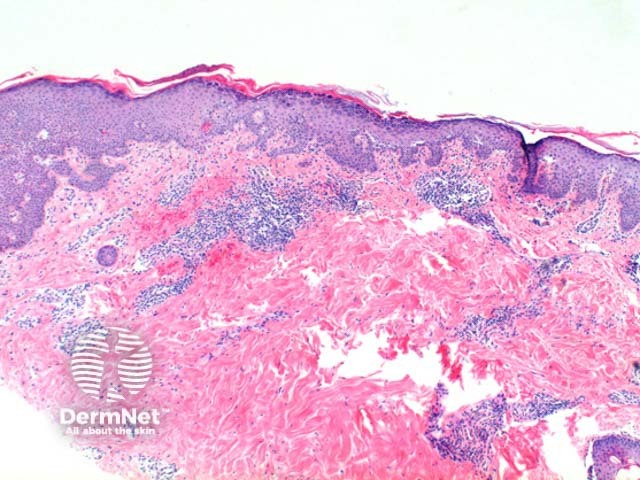

The low power view of the histology of pemphigus foliaceus is of a superficial epidermal blistering process. The low power clues include loss of the stratum corneum, increased prominence of the granular layer, or visible superficial epidermal separation with blister formation (Figure 1). At higher magnification subtle acanthloysis and spongiosis can be seen within the stratum granulosum, extending into the stratum corneum (Figures 2 and 3). This can form separation within the superficial epidermis, or as mentioned above, lead to complete loss of the stratum corneum. The prominent granular layer is seen as hyperchromasia of the nuclei within dyskeratotic cells in this layer, similar to the grains seen in Dariers disease (Figures 4 and 5).

In the dermis there is a predominantly superficial lymphocytic infiltrate with scattered eosinophils (Figure 3). Neutrophils may be more common in the IgA subtype.

Figure 1